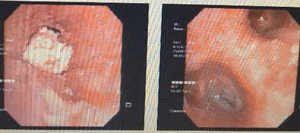

Một bệnh nhân bị đau bụng, nghĩ mình bị đau dạ dày hay đại tràng nên đi khám thì được các bác sỹ phát hiện “vật thể lạ” là một chiếc tăm tre cắm vào thành dạ dày của bệnh nhân.